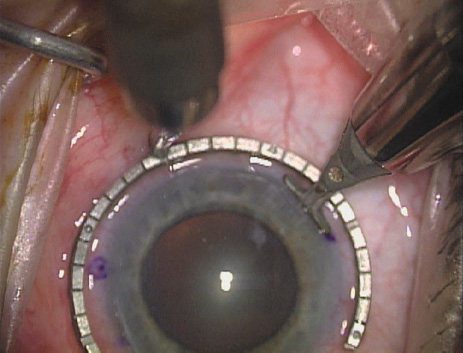

Case 2 is a 79-year-old woman who presented with a very dense left cataract. Her refraction was recorded at −2.25 +2.75 × 125 with a difficult end point. Her manual keratometry and topography measurements were consistent and revealed slightly less than 1.75 D at 120 degrees. Because of the questionable refraction, greater value was placed on the corneal measurements. Based upon the cataract nomogram, the plan was for paired LRIs of 40 degrees to be placed over the steep 120-degree axis (Figs. 1219).

Fig. 12. In this left eye, the steep meridian is at the 120-degree axis and has been delineated by opposing limbal marks. The upper left hand ink mark represents the 6:00 position for orientation. (Reprinted from Hardten DR, Lindstrom RL, Davis EA. Phakic Intraocular Lenses: Principles and Practice. Thorofare, NJ: SLACK Incorporated, 2004, with permission.)

Fig. 13. The incision is begun 20-degrees to one side of the centering mark. (Reprinted from Hardten DR, Lindstrom RL, Davis EA. Phakic Intraocular Lenses: Principles and Practice. Thorofare, NJ: SLACK Incorporated, 2004, with permission.)

Fig. 14. The incision is completed. (Reprinted from Hardten DR, Lindstrom RL, Davis EA. Phakic Intraocular Lenses: Principles and Practice. Thorofare, NJ: SLACK Incorporated, 2004, with permission.)

Fig. 15. Total arc length equals 40 degrees. (Reprinted from Hardten DR, Lindstrom RL, Davis EA. Phakic Intraocular Lenses: Principles and Practice. Thorofare, NJ: SLACK Incorporated, 2004, with permission.)